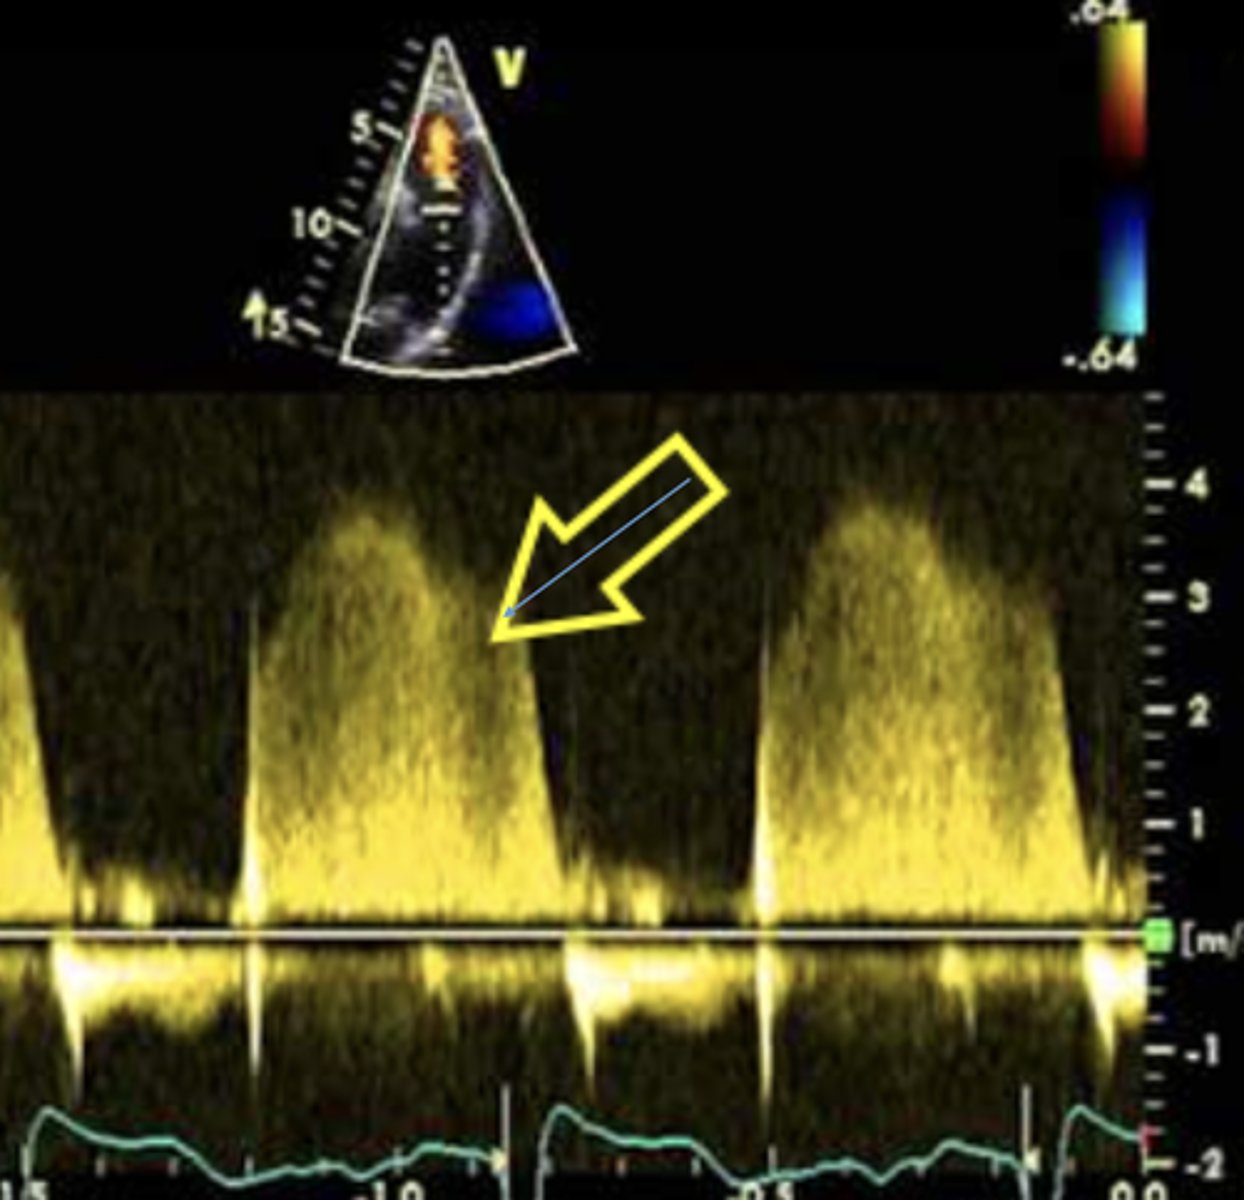

Spectral Doppler Features of Severe PR

Brighter/denser signal

Rapid deceleration

Pressure Half Time for PR

Calculated from deceleration time tracing of the slope

Shorter PHT = more severe PR

PHT or DT for Severe PR

< 100 msec or < 260 msec